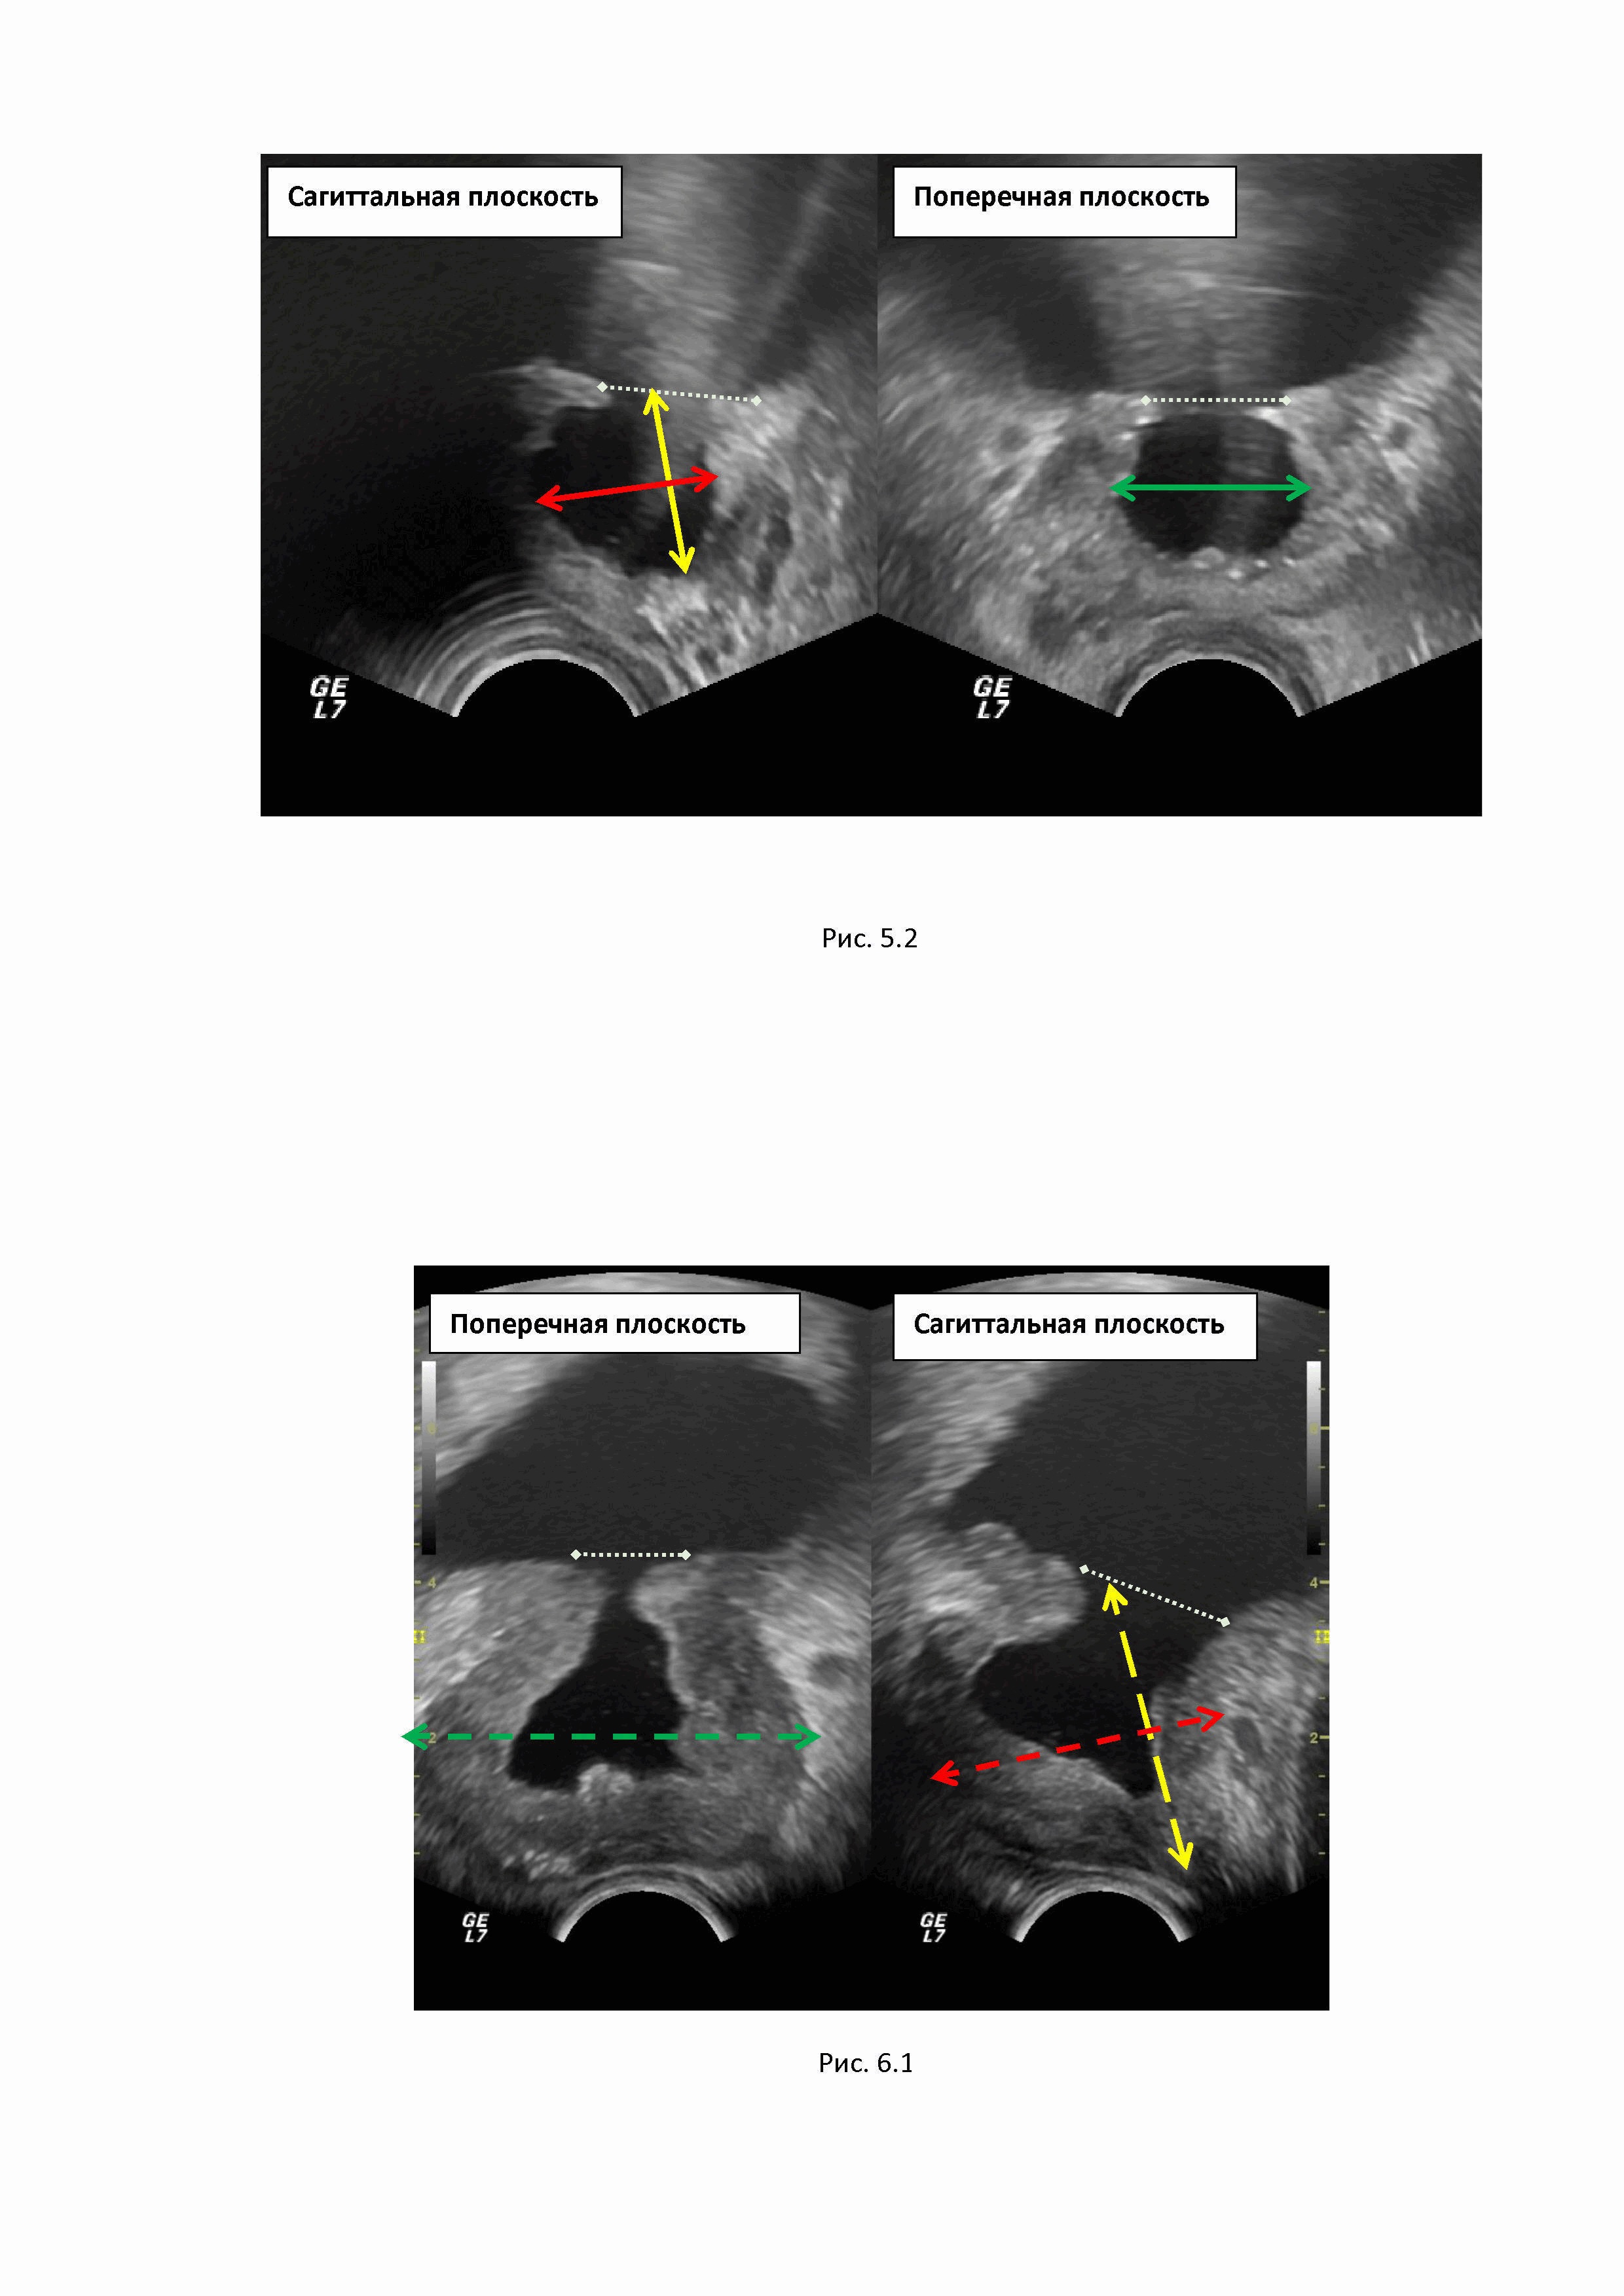

Изобретение относится к области медицины, в частности к ультразвуковой диагностике, и предназначено для улучшения количественной оценки остаточного объема ткани предстательной железы после ее резекции. Способ обеспечивает получение количественных показателей остаточного объема ткани резецированной простаты, что позволит вычислять плотность ПСА, значение которого в настоящее время расцениваются как один из надежных предикторов ранней диагностики рака простаты при динамическом наблюдении за больным. Точность измерения объема предстательной железы (простаты) приобрела принципиальную важность благодаря результатам последних исследований, в ходе которых было установлено, что наибольшей корреляцией среди лабораторных показателей и вероятностью рака простаты обладает показатель плотности ПСА (10, 12). Плотность ПСА рассчитывается как отношение значения исходной концентрации сывороточного общего ПСА к объему предстательной железы (2, 11, 13), а именно: где ПСА-D – плотность ПСА (от английского «PSA density»), На сегодняшний день именно плотность ПСА признается большинством экспертов одним из самых надежных прогностических критериев диагностики рака предстательной железы (РПЖ). При этом пороговым значением ПСА-D считается уровень 0,151 нг / мл / см3 (5). Однако у большой части мужчин старшей возрастной группы предстательная железа увеличивается в размерах, что требует хирургического лечения. Патологоанатомические изменения преимущественно наблюдаются в центральных отделах простаты, где формируется аденоматозная трансформация ткани (гиперпазия простаты, или аденома простаты). Аденоматозная ткань занимает центральную часть предстательной железы и деформирует шейку мочевого пузыря. Это приводит к формированию клинических проявлений аденомы простаты – дизурических жалоб и, что самое главное, к формированию нарушения опорожнения мочевого пузыря, которое, в конечном итоге, может стать причиной развития уремии. Исторически известен метод хирургического лечения данного состояния – чрезпузырная аденомэктомия по Федорову–Фрейеру. Аденомэктомия по Федорову-Фрейеру, несмотря на множество других предложенных методов лечения, относится к основным и наиболее радикальным методам лечения аденомы предстательной железы (1, 8). Несмотря на многочисленные модификации, техника данного оперативного вмешательства остается прежней (7, 9). При операции Федорова-Фрейера аденоматозные ткани удаляются вместе с пузырно-уретральным сегментом и предстательным отделом уретры одним блоком. В ходе операции образуется свободная полость в центральной части простаты, так называемый предпузырь, и его объем соответствует массе удаленных тканей простаты. При этом образуется тканевой дефект, соответствующий по форме эллипсу, диаметром от 3 см, а иссеченный край мочевого пузыря является границей его ложа. Боковыми и задней стенками служат остаточные ткани простаты, нижняя граница предпузыря располагается на уровне семенного бугорка (6). Проблема определения остаточного объема резецированной предстательной железы связана с отсутствием объективной формулы для подсчета объема железы в послеоперационном периоде по причине изменения ее конфигурации после хирургического лечения. На рис.1 представлены этапы трансуретральной резекции центральной части простаты (аденомэктомии): 1.1. Резектоскоп введен в уретру. 1.2. Этап удаления аденоматозной ткани в центральной части простаты. 1.3. Завершение операции с формированием остаточной полости (предпузыря) и сохранением периферической части простаты. Имеющиеся формулы подсчета объема неоперированной железы подразумевают форму простаты, близкую к объемному эллипсу. После проведения резекции конфигурация простаты меняется за счет удаления ткани в ее центральных отделах и формирования предпузыря округлой формы, что не позволяет объективно измерить объем органа. Известный способ определения объема простаты с использованием ультразвуковой диагностики (4) и МРТ (3, 5). При проведении магнитно-резонансной томографии малого таза определение размеров предстательной железы является необходимым условием, помимо указания её размеров современные тенденции требуют и определения объёма простаты. Для определения размеров железы используются Т2-взвешенные изображения (Т2-ВИ), за счёт высокой контрастности полученных изображений, что позволяет чётко дифференцировать анатомические границы железы (3). Измерения производят в двух взаимно перпендикулярных плоскостях: сагиттальной и аксиальной (или поперечной) (рис.2). Границы и срезы выбираются в каждом случае врачом-рентгенологом индивидуально в зависимости от формы железы, её анатомических особенностей, выраженности гиперпластических изменений в транзиторной зоне. В сагиттальной плоскости от основания до апекса простаты измеряются ее продольной размер (А), в средней трети железы измеряются передне-задний размер железы (В), а поперечной плоскости измеряют ширину простаты (С). Согласно рекомендациям PI-RADS v2.1, измерение объема предстательной железы ПЖ проводится вручную на основе формулы объема эллипсоида или с помощью автоматических алгоритмов измерения объема (5). V простаты =А х В х С х 0.523, где А – продольный размер, В – переднезадний размер, С – ширина простаты, 0.523 – поправочный коэффициент для вычисления объема эллипсоида. Использование единого подхода к расчету объема предстательной железы с помощью формулы объема эллипсоида имеет особое значение. В PI-RADS v2.1 рекомендуют измерение максимального переднезаднего размера и перпендикулярного к нему продольного размера на срединных сагиттальных T2-ВИ, а максимальную ширину рекомендуют измерять на поперечных срезах в T2-ВИ (5). При проведении УЗИ простаты с целью измерения объема ПЖ также традиционно используют формулу измерения объема эллипсоида (4) V простаты =А х В х С х 0,523, где А – продольный размер простаты, В – передне-задний размер, С – ширина простаты в средней трети, 0.523 – поправочный коэффициент (14). Ультразвуковое исследование проводят в двух взаимоперпендикулярных плоскостях – сагиттальной и поперечной. В саггитальной плоскости измеряют продольный размер простаты от основания простаты до апекса железы (А), в этой же плоскости перпендикулярно продольному размеру в средней трети железы измеряют передне-задний размер (В). Далее перемещают датчик в поперечную плоскость и в средней части железы производят измерение ширины железы С, проводя измерительную дистанцию от боковых границ органа. На рис.3 представлен алгоритм измерения объема неоперированной простаты при проведении трансректального УЗИ в двух плоскостях сагиттальной и поперечной. В сагиттальной плоскости сканирования от основания до апекса железы желтым пунктиром обозначен продольный размер (А). В этой же плоскости красный пунктир, проведенный от передней границы до задней границы железы, соответствует передне-заднему размеру. В поперечной плоскости сканирования зеленый пунктир, проведенный от правой боковой до левой боковой границы простаты, соответствует ширине железы (С) в средней трети железы. После проведения резекции при хирургическом лечении аденомы простаты конфигурация простаты меняется за счет удаления ткани в ее центральных отделах, поскольку на месте удаленной ткани в центральных части железы формируется предпузырь округлой формы, что не позволяет объективно измерить объем органа. На рис.4 представлено ультразвуковое изображение, демонстрирующее остаточный, объем резецированной простаты и изменение конфигурации железы за счет формирования предпузыря на месте удаленной аденоматозной ткани (объем предпузыря обозначен белой стрелкой). Указаний на необходимость измерения предпузыря после резекции простаты методом УЗД или МРТ в доступной литературе нам не встретилось. В руководстве «Магнитно-резонансная томография предстательной железы» под ред. А.В. Мищенко дается описательная характеристика предпузыря как воронкообразного дефекта аденоматозно-измененной простаты без метрических показателей (3). В тоже время точность измерения объема приобрела принципиальную важность в последние годы благодаря результатам последних исследований, в которых была продемонстрирована значимость критерия плотности ПСА в сыворотке крови (в нг/мл), рассчитываемой как соотношение сывороточного ПСА к объему предстательной железы (11,13). На сегодняшний день именно плотность ПСА признается большинством экспертов одним из самых надежных прогностических критериев диагностики РПЖ. Технической проблемой, на решение которой направлено изобретение является разработка достоверного и простого способа определения остаточного объема резецированной простаты после аденомэктомии. Техническим результатом разработанного способа является объективизация значения остаточного объема резецированной простаты, что позволит корректно измерять плотность ПСА в остаточном объеме резецированного органа по формуле (11,13) где ПСА-D – плотность ПСА (от английского «PSA density»), Способ определения остаточного объема резецированной простаты характеризуется тем, что проводят трансректальное ультразвуковое исследование простаты, при котором последовательно производится измерение простаты целиком с целью определения объема железы, включая объем предпузыря, на следующем этапе проводят измерение и вычисление объема предпузыря, и, путем вычитания объема предпузыря из объема простаты, измеренного целиком, получают остаточный объем резецированной простаты. При осуществлении способа проводят трансректальное исследование. С этой целью микроконвексный ультразвуковой датчик частотой 7 – 9 МГц вводят в ампулу прямой кишки, предварительно изолировав его поверхность резиновым ультразвуковым наконечником для соблюдения асептики. Проводят детальную оценку предстательной железы и предпузыря. Далее приступают к проведению измерения простаты и предпузыря с целью получения показателей объема обеих структур. Измерение объема резецированной простаты целиком получают при измерении трех линейных параметров – продольного (А), передне-заднего (В) размеров и ширины ПЖ(С). На рис.5.1 представлено измерение объема резецированной простаты целиком, включая объем предпузыря. Измерение размеров производится последовательно в сагиттальной и поперечной плоскостях сканирования. В сагиттальной плоскости (левое фото) проводится желтый пунктир от границы предпузыря (белый пунктир) до апекса простаты. Граница предпузыря маркируется виртуальной замыкающей линией, от которой измерительный маркер направляется к верхушке простаты. Данный размер соответствует продольному размеру простаты А. Желтый пунктир, соответствующий передне-заднему размеру железы (В), проводится в этой же плоскости от передней к задней границе простаты. Далее измерение производится в поперечной плоскости сканирования простаты, для чего датчик размещают перпендикулярно первоначальной дистанции. В поперечной плоскости (правое фото) зеленый пунктир, проведенный от боковых границ железы, соответствует ширине простаты в средней трети железы (С). Измерение ширина простаты производят на уровне средней части простаты. На основании полученных показателей по известной формуле (4) вычисляют объем простаты вместе с предпузырем (целиком): Vпростаты целиком = А х В х С х 0,523, где А – продольный размер простаты, см, В – передне-задний размер простаты, см, С – ширина простаты, см, 0.523 – поправочный коэффициент. Второй этап. Далее приступают к измерению объема полости предпузыря. Для этого проводят линейные измерения в двух плоскостях – сагиттальной и поперечной - и получают значения продольного (a), передне-заднего (b) размеров и ширины (c) предпузыря. Продольный размер измеряют в сагиттальной плоскости, проводя измерительный маркер от замыкающей верхние границы предпузыря виртуальной линии до нижней границы предпузыря с простатой на уровне семенного бугорка. В этой же плоскости сканирования измеряют передне-задний размер предпузыря, для чего перпендикулярно к первой линии проводят измерительный маркер спереди назад по передне-задним границам предпузыря в его средней трети. Ширина предпузыря изменяется в средней части объекта в поперечной плоскости сканирования железы. На рисунке 5.2 представлено измерение объема предпузыря. От верхней границы предпузыря (белая пунктирная линия – виртуальная граница простаты в зоне резекции) проводится сплошная желтая линия до нижней границы предпузыря, что соответствует продольному размеру. Красная сплошная линия, проведенная также в сагиттальной плоскости, от передней до задней границы полости предпузыря, соответствует передне-заднему размеру. Далее датчик располагают в перпендикулярной плоскости сканирования, и получают изображение железы в поперечной плоскости. Сплошная зеленая линия, проведенная от боковых границ полости предпузыря, соответствует его ширине. На основании полученных показателей вычисляют объем предпузыря по формуле вычисления объема эллипсоида (4): Vпредпузыря = a х b х c х 0,523, где а – продольный размер предпузыря, b – передне-задний размер предпузыря, с – ширина предпузыря, 0.523 – поправочный коэффициент. Третий этап. Вычисление остаточного объема резецированной простаты. На основании проведенных измерений вычисляют остаточный объем резецированной простаты (V резецированной простаты) Vрезецированной простаты = Vпростаты целиком –Vпредпузыря или Vрезецированной простаты = (А х В х С х 0,523)– a х b х c х 0,523) Полученная величина является основой для измерения плотности ПСА-D (11,13), измерение которой проводиться по известной формуле где ПСА-D – плотность ПСА, нг/мл/см³, ПСА общ. – значения общего ПСА, нг/мл, Vост. – остаточный объем резецированной простаты, см3. Установление количественных показателей остаточного объема ткани резецированной простаты позволяет вычислять плотность ПСА. Значение плотности ПСА получают как соотношение показателя ПСА в нг/мл к объему остаточной ткани резецированной простаты в куб.см. Значение плотности ПСА в настоящее время рассматривается как важнейший фактор при динамическом наблюдении пациентов при онконасторженности (5). При получение значений ПСА-D более 0.151 пациент должен рассматриваться как потенциальный больной раком простаты с проведением стандартизированного онкологического исследования (МКБ Z03.1 Наблюдение пациента с подозрением на злокачественное новообразование). В связи с этим количественная оценка остаточного объема резецированной простаты является важнейшим условием выбора тактики ведения больного. Невозможность провести объективное измерение объема простаты после резекции традиционным способом связано с существенным изменением формы железы после операции, что не позволяет использовать в клинической практике показатель «плотность ПСА», важность которого доказана в онкоурологии. Невозможность использования в клинической практике достоверного показателя уровня плотности ПСА может привести к ложному представлению о состояния больного и выбору ошибочной тактики. Клинические примеры: №1 Больной П., 65 лет. Наблюдается урологом. Пять лет назад перенес резекцию простаты (трансуретральную аденомэктомию). ПСА в динамике 1.3 нг/мл - 2.2 нг/мл - 1.8 нг/мл. В настоящий момент ПСА 5.21 нг/мл. Жалоб активно не предъявляет. Результаты УЗИ: рис. 6.1. На первом этапе в сагиттальной плоскости измеряли объем простаты (вместе с предпузырем), для чего в сагиттальной плоскости от виртуальной границы зоны резекции мочевого пузыря (белый пунктир) проводили измерительную дистанцию до верхушки простаты (дистанция обозначена желтым пунктиром) и получили значение 4.2 см. Далее в этой же плоскости сканирования средней трети простаты проводили измерительную дистанцию перпендикулярно первому измерению от передней до задней границы железы (дистанция обозначена красным пунктиром) с получением результата 4.2 см. Далее переходили в поперечную плоскость сканирования простаты, для чего разворачивали датчик перпендикулярно предыдущему положению. Измерение ширины простаты (дистанция обозначена зеленым пунктиром) проводили от правой до левой границы простаты в средней ее трети с получением результата 5.2 см. Далее производили вычисление объема простаты целиком с объемом предпузыря по известной формуле вычисления объема эллипсоида: V простаты целиком = 4.2 х 4.2 х 5.2 х 0.523 = 47.9 см3. Измерение объема предпузыря (рис.6.2) производили в двух плоскостях - сагиттальной и поперечной. Длинник измеряли в сагиттальной плоскости от виртуальной границы предпузыря с мочевым пузырем (белый пунктир) до нижней границы (желтая сплошная линия) с получением результата 2.4 см. В это же плоскости сканирования получали передне-задний размер предпузыря, проводя линию в средней части предпузыря от передней до задней его границы (красная сплошная линия) с получением результата 2.3 см. Измерение ширины предпузыря проводили в поперечной плоскости сканирования, изменив положение датчика на перпендикулярное начальному и проводя измерительный маркер от правой до левой границы предпузыря (зеленая сплошная линия) с получением результата 2.3 см. Далее вычисляли объем предпузыря по известной формуле объема эллипсоида: Vпредпузыря = 2.4 х 2.3 х 2.3 х 0.523= 6.6 см3. Остаточный объем резецированной простаты вычисляли путем вычитания объема предпузыря из объема простаты целиком с получением результата: Vрезецированной простаты =Vпростаты целиком –Vпредпузыря = 47.9 –6.6= 41.3 см3. Плотность ПСА (ПСА-D) вычисляли путем деления показателя ПСАобщ. в нг/мл на остаточный объем резецированной простаты (Vрезецированной простаты) в куб. см: ПСА-D = 5.21 нг/мл : 41.3 см3 = 0.126 нг/мл/ см3. Поскольку полученные результаты плотности ПСА соответствуют нормальному значению (норма до 0.151), больному было предложено динамическое наблюдение, за время которого данных за онкологический процесс выявлено не было. № 2 Больной Л., 72 лет. Двенадцать лет назад перенес радикальную аденомэктомию по поводу гиперплазии простаты. Динамически не наблюдался. В настоящее время обратился к урологу по поводу жалоб на умеренную болезненность при мочеиспускании. ПСА 3.83 нг/мл. С целью выявления патологии простаты проведено УЗИ. Определяли объем простаты целиком. С этой целью при проведении трансректального УЗ-сканирования сагиттальной плоскости (рис.7.1) проводили измерительный маркер (желтый пунктир) от виртуальной границы предпузыря с мочевым пузырем (белый пунктир) до верхушки простаты, получив значения длинника простаты 3.5 см. В этой же плоскости проводили измерение передне-заднего размера простаты, для чего проводили измерительный маркер (красный пунктир) от передней до задней границы простаты в средней трети органа с получением результата 3.3 см. Для измерения ширины простаты переводили датчик в перпендикулярное положение, и в поперечной плоскости сканирования на уровне средней трети простаты проводили измерительный маркер (зеленый пунктир) от правой до левой границы железы, получив результат 5.0 см. Объем простаты целиком (вместе с предпузырем) вычисляли по известной формуле объема эллипсоида: V простаты целиком = 3.5 х 3.3 х 5.0 х 0.523 = 30.2 куб.см. Объем предпузыря вычисляли в двух плоскостях (рис.7.2): длинник предпузыря и передне-задний размер пузыря получали при сканировании в сагиттальной плоскости. Для получения размера длинника проводили измерительный маркер (желтая сплошная линия) от виртуальной границы предпузыря (белый пунктир) до проекции нижней границы предпузыря (проекция семенного бугорка) с получением размера 2.6 см. Далее измеряли переднее-задний размер предпузыря, для этого измерительный маркер (красная сплошная линия) проводили перпендикулярно первой дистанции в направлении от передней до задней границы предпузыря с получением результата 2.2 см. Следующим этапом сканирования было получение показателя ширины предпузыря в поперечной плоскости сканирования железы. Для этого измерительный маркер (зеленая сплошная линия) проводили в средней части простаты от правой до левой границы предпузыря с получением результата 2.3 см. Вычисление объема предпузыря проводили по формуле объема эллипсоида: Vпредпузыря = 2.6 х 2.2 х 2.3 х 0.523=6.9 куб.см. Вычисление остаточного объема резецированной простаты проводили путем вычитания объема предпузыря из объема простаты целиком. Vрезецированной простаты = Vпростаты целиком - Vпредпузыря = 30.2 – 6.9 = 23.3 см3. Плотность ПСА вычисляли путем деления показателя ПСАобщ. в нг/мл на остаточный объем резецированной простаты (Vрезецированной простаты): ПСА-D=3.83 нг/мл : 23.3 куб.см = 0.164 нг/мл/см3. Полученный результат превышал допустимое значение (норма до 0.151), и пациенту был поставлен диагноз: Z03.1. Наблюдение пациента с подозрением на злокачественное новообразование, что потребовало развернутого онкологического обследования - была проведена компрессионная соноэластография, в левой доле выявлен очаг высокой ригидности, что свидетельствует о наличии злокачественного процесса. Выполненная МРТ подтвердила наличие патологического очага левой доли резецированной простаты. Проведена трансректальная пункционная биопсия под УЗ-наведением. По данным биопсии: аденокарцинома, Gleason sum 3+3= 6. Больной направлен на консультацию к урологу-онкологу для выработки дальнейшей тактики лечения. Литература 1. Доброкачественная гиперплазия предстательной железы. Под ред. Н.А. Лопаткина. М., 1997. 2. Кнеев А.Ю., Школьник М.И., Богомолов О.А., Вершинская Ю.Г., Жаринов Г.М. Плотность простатспецифического антигена как прогностический маркер у больных локализованным раком предстательной железы. Урологические ведомости. 2021, Том 11, № 3, стр. 205-212. 3. Магнитно-резонансная томография предстательной железы / Дубицкий Д., Мищенко А. В., Л., Трофименко И. А. – Москва: ГОЭТАР-Медиа, 2021. - 528 с. 4. Назаренко Г.И., Хитрова А.Н. Ультразвуковая диагностика предстательной железы в современной урологической практике. – Москва: Издательский дом «Видар-М», 2012. – 288 с. 5. Рубцова Н. А., Мищенко А. В., Данилов В. В., Гулин Г. А., Алексеев Б. Я., Каприн А. Д. PI-RADS v2.1: движение на пути к ясности (комментарии к обновленной версии). Онкоурология, 2020, № 2, т.16, стр. 151-28. 6. Сергиенко Н.Ф., Василенко М.И., Кудряшов О.И. Классическому радикальному экстрауретральному способу аденомэктомии более 30 лет», Урология. 2015, № 4, стр.39-43. 7. Сергиенко Н.Ф., Василенко М.И., Кудряшов О.И. К вопросу о так называемом «золотом стандарте» оперативного лечения аденомы предстательной железы. Урология, 2021, № 4, стр. 69-72. 8. Степанов В.Н. Симптоматика и клиническое течение доброкачественной гиперплазии предстательной железы. В кн.: Доброкачественная гиперплазии предстательной железы. Под ред. Н.А. Лопаткина. М., 1997. С. 41–45. 9. Урология: учебник/ Б.К. Комяков. М.: ГОЭТАР-Медицина, 2011. – стр.309-317. 10. Dong F. et al. Validation of pretreatment nomograms for predicting indolent prostate cancer: efficacy in contemporary urological practice. J Urol 2008;180:150. 11. Lee S.J., Oh Y.T., Jung D.C. et al. Combined analysis of biparametric MRI and prostate-specific antigen density: role in the prebiopsy diagnosis of Gleason score 7 or greater prostate cancer. AJR Am J Roentgenol 2018;211(3):W166–72. DOI: 10.2214/AJR.17.19253. 12. Loeb S. et al. Active surveillance for prostate cancer: a systematic review of clinicopathologic variables and biomarkers for risk stratification. Eur Urol 2015;67:619. 13. Mehralivand S., Shih J.H., Rais-Bahrami S. et al. A magnetic resonance maging-based prediction model for prostate biopsy risk stratification. JAMA Oncol 2018;4(5):678–85. DOI: 10.1001/jamaoncol.2017.5667 14. Terris M.K., Stamey T.A. Detrmination of prostate volume by transrectal ultrasound. J.Urol.1991; 145 (5);984-987.